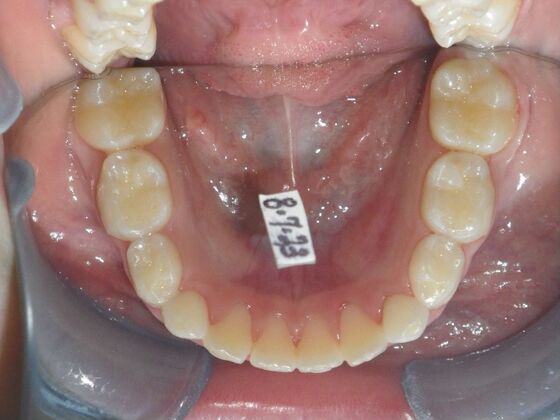

Patient presents with delayed eruption of the upper right central incisor and lower anterior crowding. Treatment plan to include exposure of right central incisor with bracket placement and correction of lower anterior crowding.